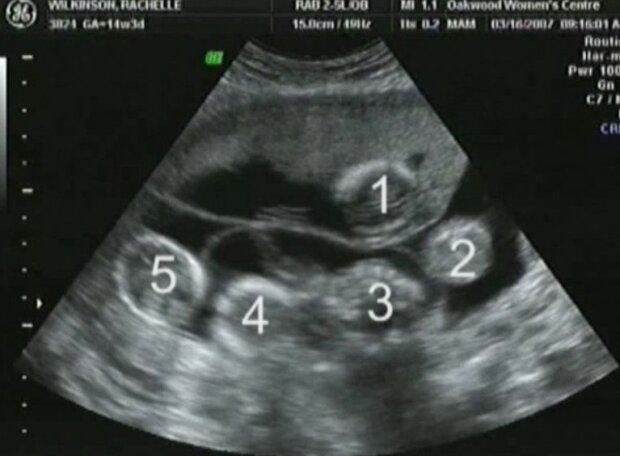

Zatímco ještě těhotná Varvara šla na ultrazvuk a tam se ukázalo, že pod srdcem ženy nosí dokonce pět embryí. Lékaři byli znepokojeni tímto stavem věcí a navrhli páru odstranit dvě embrya, aby se v budoucnu zabránilo rizikům. Ale Artamkinovi jsou věřící, odmítli to udělat a rozhodli se, že jak Bůh dá.